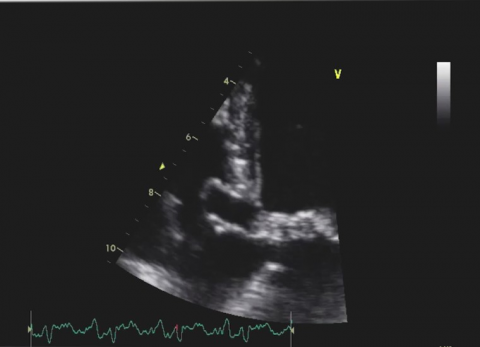

Wideo Echokardiografia. Przypadek 29

prof. dr hab. n. med. Zbigniew GąsiorPacjent ze spoczynkowymi bólami zamostkowymi i gorączką od kilku dni. Pacjent z niewydolnością serca z obniżoną frakcją wyrzutową.